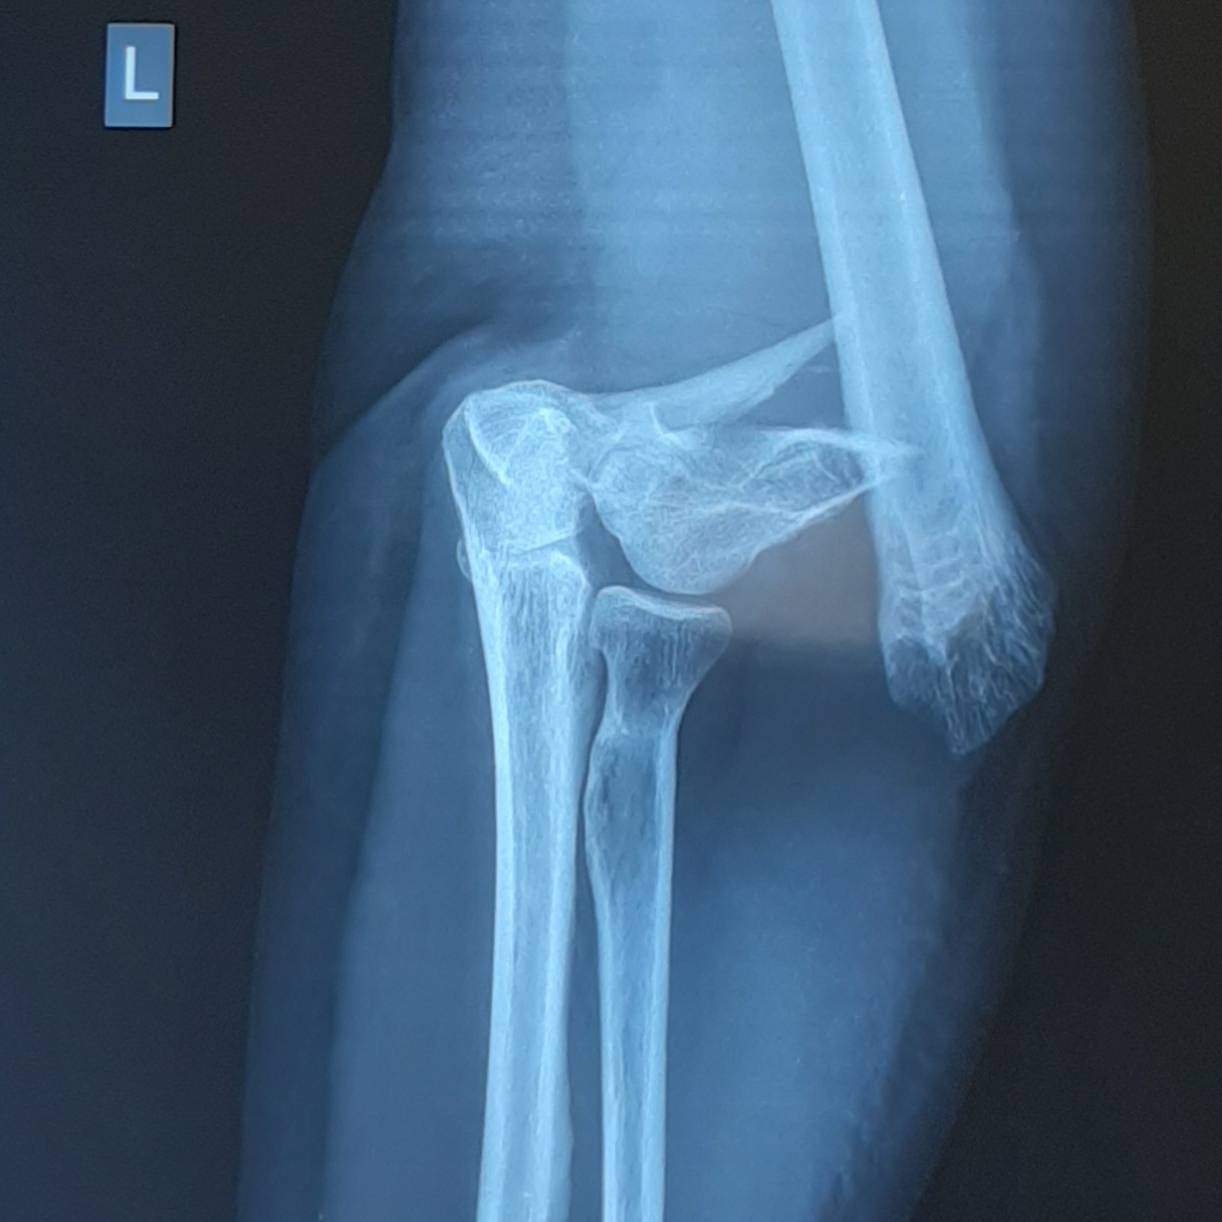

Пациентка Х, 54 лет, получила внутрисуставной Y-образный перелом мыщелков плеча. Смещение костных отломков настолько значительно, что диафиз плечевой кости близок к тому чтобы перфорировать кожу.

В случае настолько грубого смещения при первичном осмотре целесообразно выполнить анестезию перелома и устранить смещение с фиксацией конечности в задней гипсовой лонгтеной повязке. После обследования и предоперационной подготовки пациентка взята в операционную. Выполнен остеосинтез при помощи пластин с угловой стабильностью Synthes.